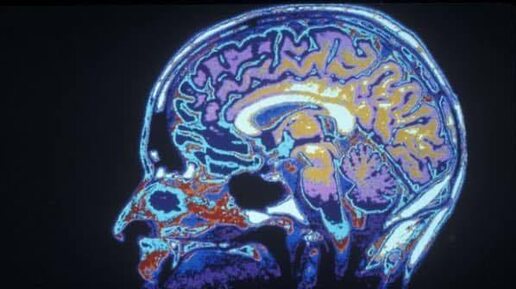

Когда заканчивается детство, непосредственно перед пубертатным периодом, наблюдается второй период интенсивного роста: в префронтальной коре

Когда заканчивается детство, непосредственно перед пубертатным периодом, наблюдается второй период интенсивного роста: в префронтальной коре возникают новые связи (синапсы), формируя новые пути За этим ростом следует десятилетие активной «обрезки»: в течение всего подросткового периода слабые связи удаляются, а сильные укрепляются В результате этого прореживания объем префронтальной коры уменьшается приблизительно на 1 % в год вплоть до окончания пубертатного периода Поскольку эти масштабные...